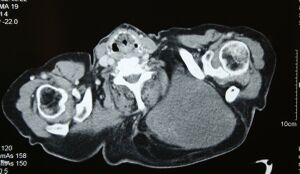

التصوير الطبي

قد لا يكون التصوير بالموجات فوق الصوتية قادراً على التمييز بين الغرن الشحي والورم الشحمي الحميد، وبالتالي، فإن التصوير بالرنين المغناطيسي هو التصوير الأولي المفضل.[4]

-

Medical ultrasonography of a liposarcoma: In this case a heterogeneous mass consisting of an upper hyperechoic portion, corresponding to lipomatous matrix, and areas of hypoechogenicity corresponding to nonlipomatous components.[5]